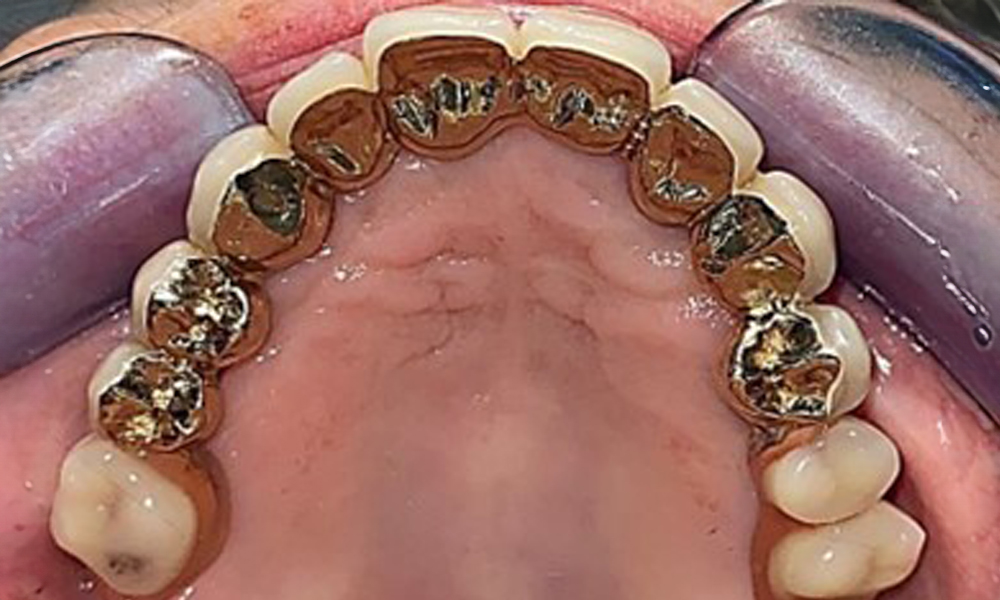

Die Patientin wurde vor über 25 Jahren mit einer kombinierten herausnehmbare Implantat-Teleskopprothese im Oberkiefer versorgt (Abb. 1, Abb. 2, Abb. 3) und ist sehr glücklich über ihren Zahnersatz. Im Unterkiefer hat die Patientin einen suffizienten festsitzenden Zahnersatz. (Abb. 4)

Der dentale Befund stellt sich wie folgt dar: Kombinierte herausnehmbare Implantat- und zahngetragene Teleskoparbeit auf Implantaten 15, 13, 21, 23, 24, 25 und Zahn 11 (Abb. 1, Abb. 2, Abb. 3). Im Unterkiefer ist die Patientin mit einem festsitzenden Zahnersatz versorgt. 37–34 sowie 45–47 haben suffiziente Brücken (Abb. 4). Kronenränder sind intakt, aktive kariöse Läsionen sind nicht vorhanden. An Zahn 43 zeigt sich eine Compositefüllung mit Randspalt. Im Unterkiefer liegen Rezessionen mit freiliegender Wurzeloberfläche zwischen 1 – 3 mm vor. Dies trifft auch für 11 zu.